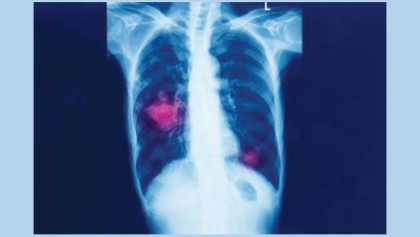

Not all disease is easy to spot. Yok_onepiece/Shutterstock